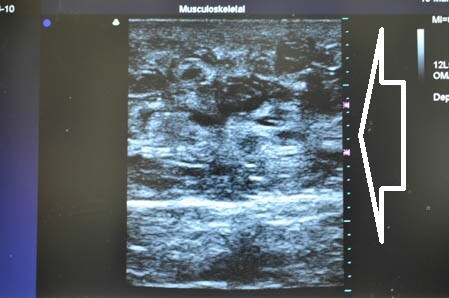

さて今回は3Dタッチビュー(=超音波)

を用いて皮下脂肪層の状態を

適宜チェックしながらの手術になりました。

上腹部の皮下脂肪の状態を

手術直前と直後で比較して見てみましょう。